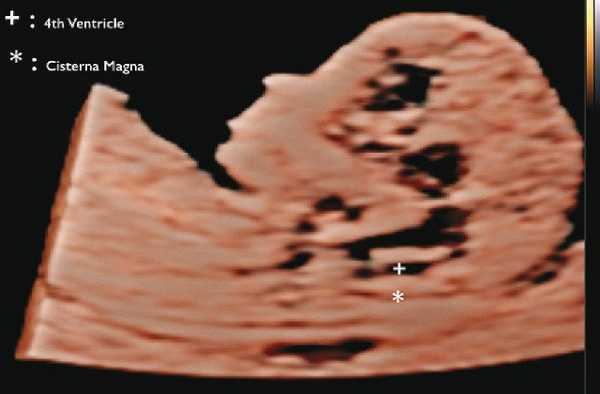

В прошлом лечащие врачи и врачи ультразвуковой диагностики проводили ультразвуковой скрининг для выявления дефектов нервной трубки, главным образом открытого расщепления позвоночника (spina bifida), во II триместре. В последние годы предложены ранние ультразвуковые маркеры на 11-14-й неделе беременности (внутричерепное пространство, использование БПР и соотношения БПР/ПРЖ (поперечный размер живота)), которые позволяют выявить у некоторых плодов высокий риск открытого расщепления позвоночника (рис. 7) 11.

Рис. 7. Внутричерепное пространство при ультразвуковом скрининге по поводу открытого расщепления позвоночника.